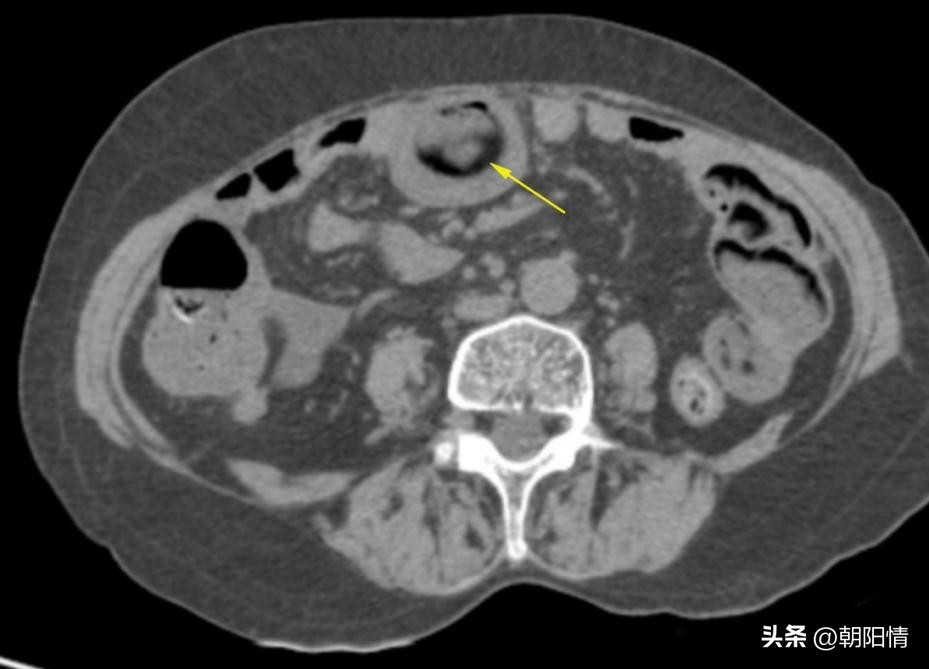

Case10:男性,17岁,腹痛半天就诊,临床可疑急性阑尾炎。行全腹部CT检查:

影像所见:线状异物穿破盲升结肠肠壁及腹膜,累及右侧腹壁肌肉,局限性腹膜炎。

腹腔镜手术证实异物为牙签,肠周、右侧结肠旁沟积脓。